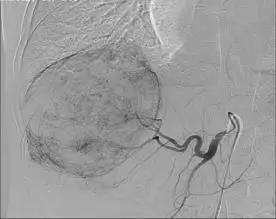

栓塞術(shù)中顯示的肝部腫瘤與栓塞術(shù)后CT顯示的腫瘤對(duì)比

“這種情況不宜切除右半肝臟,因?yàn)樽蟀敫误w積小,余肝不能代償,切除后會(huì)導(dǎo)致肝功能衰竭,危及生命。必須先行介入治療,把供應(yīng)肝臟腫瘤的血管堵死,‘餓死’癌細(xì)胞,使癌瘤縮小,左肝代償增大,待肝癌降期后再行手術(shù)治療,效果會(huì)比較好,也比較安全。”濰坊市市立醫(yī)院普外科主任醫(yī)師遲景濤分析說(shuō)。

劉大爺住院期間共經(jīng)過(guò)“經(jīng)皮經(jīng)股動(dòng)脈穿刺肝動(dòng)脈選擇性造影并肝癌灌注化療栓塞術(shù)”介入治療兩次,巨大肝癌明顯減小,普外專家團(tuán)隊(duì)擇期為其進(jìn)行了手術(shù),而且又成功實(shí)施了肝第Ⅶ段、第Ⅵ段切除手術(shù)。劉大爺康復(fù)出院時(shí)精神抖擻,滿面笑容,還滿意的說(shuō)癌癥再厲害也敵不過(guò)濰坊市市立醫(yī)院普外科專家的手術(shù)刀!